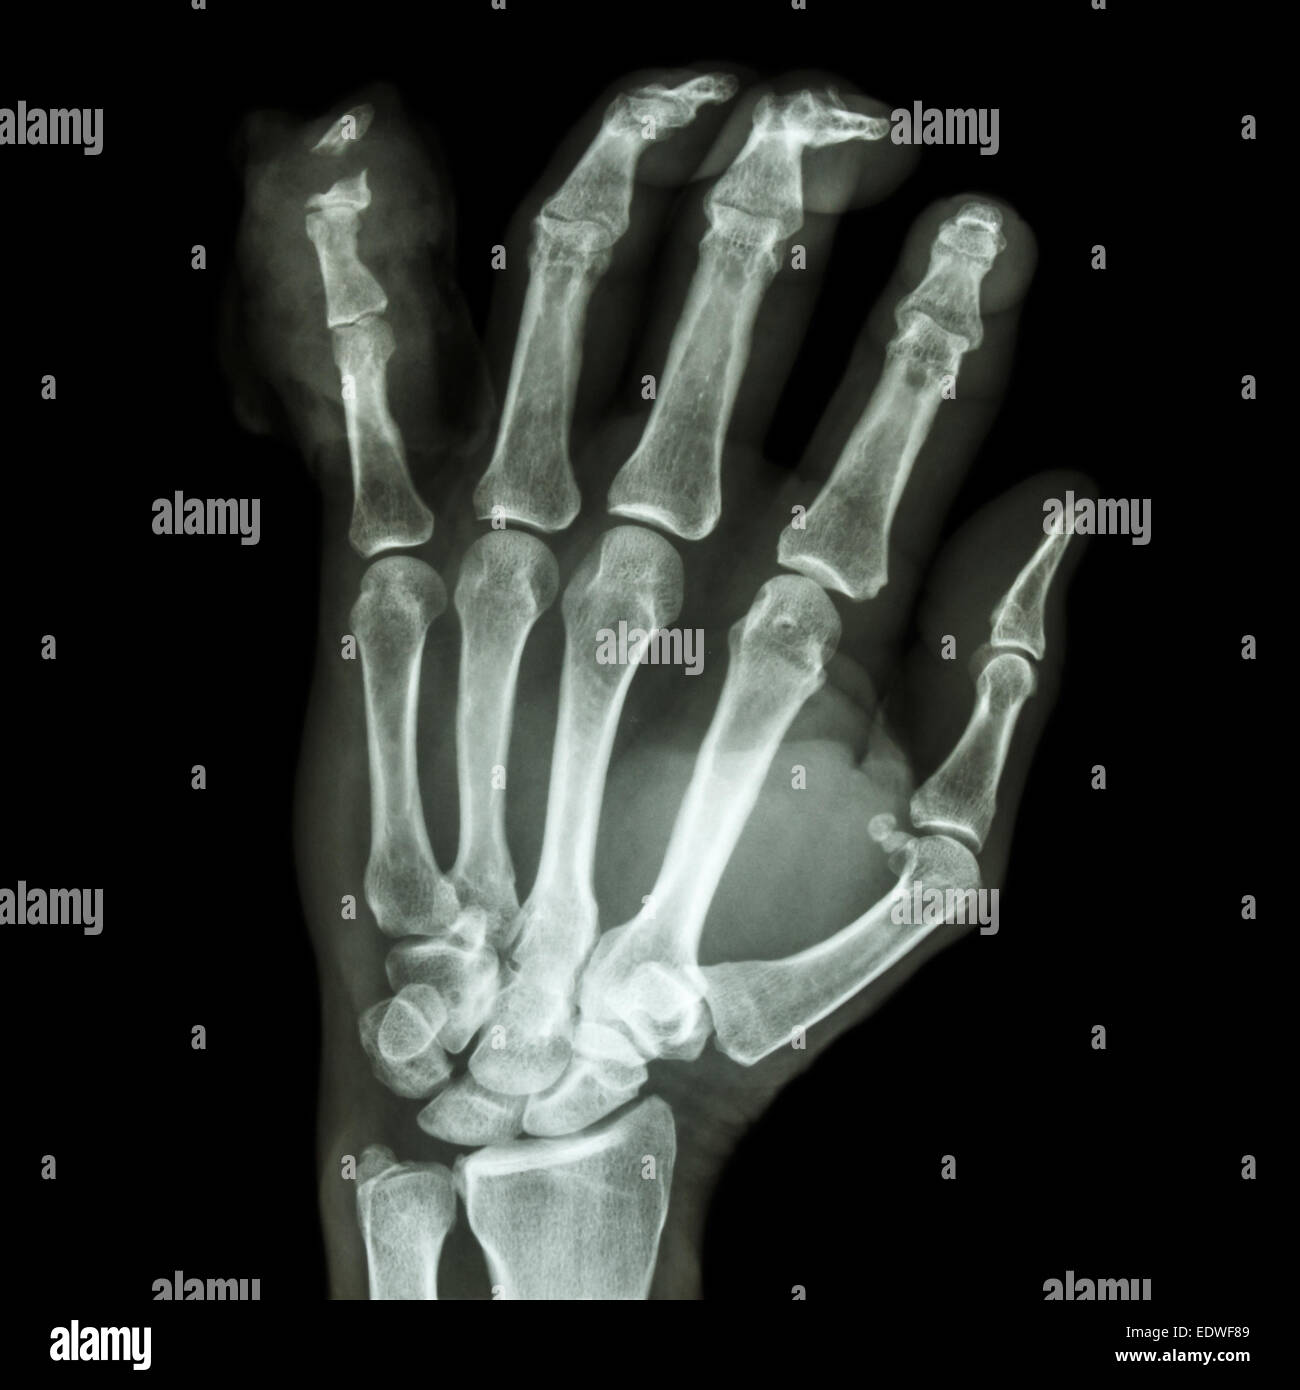

Broken Finger Bone X Ray . These bones are called phalanges, and an individual bone. The diagnosis of a broken hand generally includes a physical. While most finger fractures have simple treatments, others may require surgical intervention. It may be 3 to 4 months. a broken finger or thumb usually heals within 6 to 8 weeks, but it can take longer. The hand comprises the metacarpal and phalangeal bones. a finger fracture, or broken finger, is a break of one or more finger bones. signs of a broken finger may include pain, bruising, swelling, and/or the inability to move the finger. An urgent care facility or an emergency department. Fractures and dislocations are usually straightforward to identify, so long as the potentially injured bone is fully visible in 2 planes. If you think you have a broken finger, it's important to get it checked out.